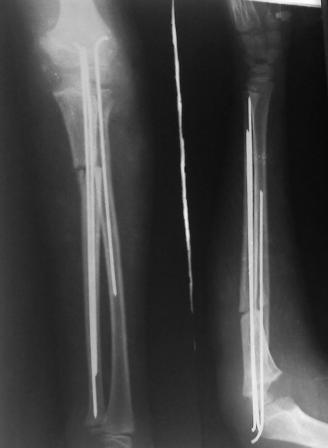

Многоуважаемые коллеги, всем большое спасибо!!! Да, здесь было повреждение Монтеджиа, когда нарисовал скиаграмму все стало понятно. Мне очень понравились рекомендации Константина Требухина, только немножко видоизменил; я считал так, если деформацию исправить то локт/кость должна удлиниться, и во вторых, если на аппарате низвести лучевую кость, то может наступить позиционное несоответствие в дистальном радиоульнарном сочленении. 28.02.08г операция - шарнирная остеотомия локтевой кости на уровне деформации, далее вскрыт плечелучевой сустав, удалены рубцовые тканы, после исправления варусной деформации и создания физиологического изгиба локтевой кости головка луча легко вправился, из части рубцовой ткани сделана пластика кольцевндной связки, трансартикулярная фиксация спицей, локтевая кость двумя спицами.